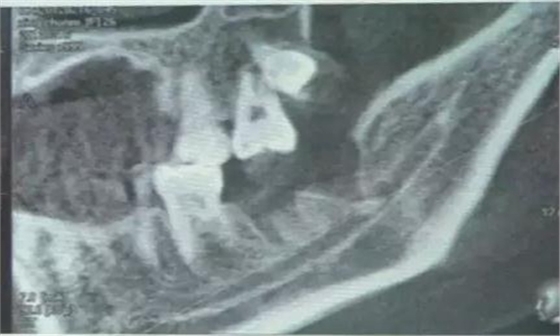

下面看一個(gè)病例,患者,女,30歲,因左下頜智齒嵌塞食物后疼痛,至當(dāng)?shù)匮揽平o予拔除,但術(shù)后1個(gè)半月,患者自覺(jué)拔牙區(qū)一直隱隱疼痛,時(shí)輕時(shí)重,遂來(lái)診。檢查發(fā)現(xiàn),拔牙創(chuàng)口一直未愈合,未見(jiàn)明顯腫脹,拍片發(fā)現(xiàn),拔牙窩內(nèi)顯示高密度斷根影

像,該斷根臨近下頜神經(jīng)管,同時(shí)發(fā)現(xiàn)第二磨牙遠(yuǎn)中有兩塊高密度影像,疑似殘留骨片或牙片,應(yīng)該是引起疼痛的原因,經(jīng)與患者溝通,采納建議,進(jìn)行二次拔牙。

術(shù)中拍片發(fā)現(xiàn),還有剩余,繼續(xù)。。。。